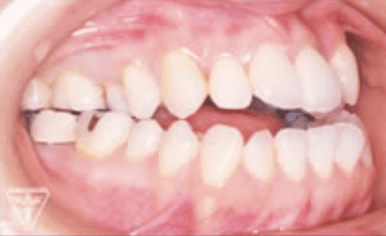

治療前、装置装着直後

治療後

治療前後の比較